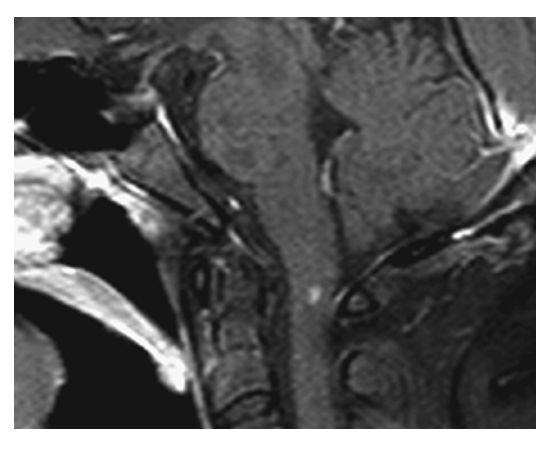

Neurovascular Compression Syndrome. MRA-TOF shows contact between the left posterior cerebral artery (PCA) (short arrow) and the left trigeminal nerve CN 5 (long arrow). In this individual, the vascular loop induced trigeminal neuralgia.